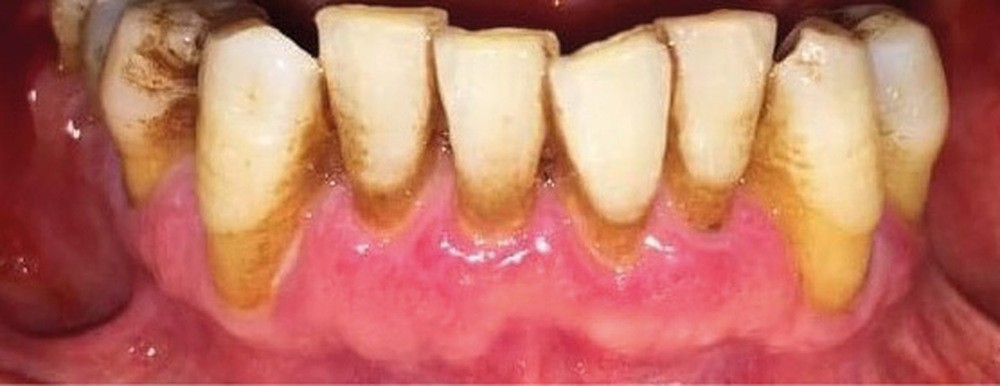

À l’interrogatoire, le patient affirme qu’il a des difficultés à maintenir une hygiène bucco-dentaire satisfaisante du fait des douleurs, et n’a pas pu consulter son chirurgien-dentiste pour son détartrage annuel en raison de la crise sanitaire en cours. L’examen clinique révèle une parodontite chronique (stade 3) généralisée et des lésions jugales (fig. 1 et 2), labiales (fig. 3) et gingivales (fig. 4) érythémateuses et kératosiques. Les lésions kératosiques jugales sont de type réticulé (fig. 1 et 2) ; les lésions kératosiques labiales sont associées à de petites érosions (fig. 3) ; les lésions palatines à des ulcérations (fig. 5). La langue présente une lésion blanche en « tache de bougie » (fig. 6) ; la muqueuse du plancher buccale est saine (fig. 7). Le signe de la pince est négatif. Le patient n’est pas porteur de prothèse dentaire malgré un édentement de moyenne étendue. Aucune lésion cutanée ou génitale n’est rapportée par le patient.

Le diagnostic le plus probable est le lichen plan (LP). On note, au niveau jugal, une kératinisation en réseau marquée par les stries de Wickman. Un phénomène de Koebner (exacerbation…